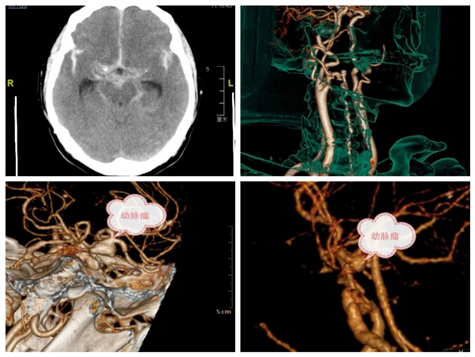

患者60岁女性,突发剧烈头痛伴恶心,至昆山市第五人民医院就诊,头部CT:蛛网膜下腔出血,急诊转至我院急诊,入院后患者昏迷,紧急气管插管,查头颈部CTA:后交通动脉瘤破裂出血入院时患者昏迷,贡伟一副主任医师会诊后紧急行开颅动脉瘤夹闭手术,术后转入ICU,现患者病人平稳,转入我科继续治疗。

患者53岁男性,突发头疼伴意识障碍急诊至我院就诊,查头部CT提示基底节脑出血伴蛛网膜下腔出血,完善头颈部CTA提示右侧大脑中动脉瘤破裂出血。22时40分在手术室的协助下,由李晓良副主任医师和何豹主治医师紧急手术治疗,经过抢救后,于凌晨4点完成手术,转入ICU进一步治疗,现患者病情平稳,转入我科进一步治疗中。

患者44岁男性,突发头疼不是1.5小时至急诊就诊,查头部CT提示蛛网膜下腔出血,进一步完善头颈部CTA提示颈内动脉突发颅内动脉C7段动脉瘤破裂出血,家属沟通后,急诊手术治疗,张曙光主任医生和李晓良副主任医师经过3个多小时的紧急手术,术后拔除气管套管回普通病房,术后第二天患者完全清醒,现在患者恢复良好,择期出院。